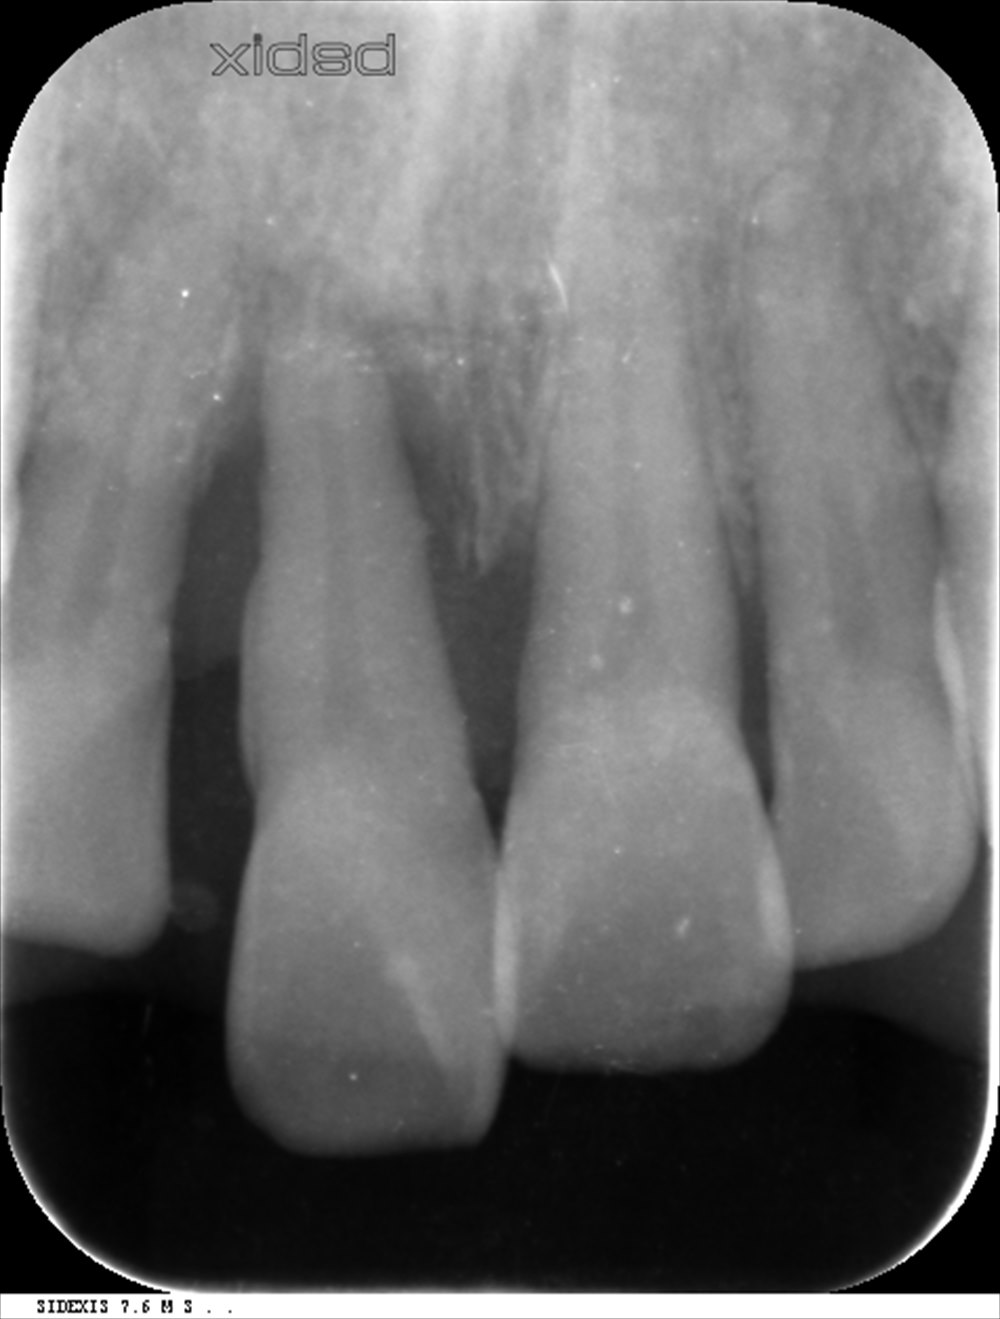

こちらが基本治療を行い、再生治療後6ヶ月のレントゲンです。

再生が認められます。

歯周ポケットも12mmから4mmに改善出血がない状態です。